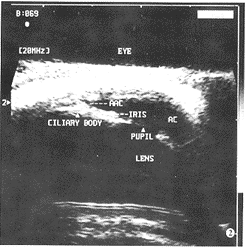

图1 正常眼前节 20.0 MHz超声图:角膜呈一条弧形高回声,前 房为无回声,虹膜呈短条状高回声,晶状体前后囊膜呈弧形高回声,晶状体内部呈无回声(AC- 前房,IRIS-虹膜,LENS-晶体)

图2 20.0 MHz超声示正常眼房角结构:睫状体为类似三角形高回 声,前房为无回声,前房角由角膜、角巩膜缘、巩膜、虹膜构成(AAC-前房角,CILIARY BODY- 睫状体,PUPIL-瞳孔)

一、正常人眼前节结构的 20.0 MHz超声表现(图1,2)

角膜厚度为(0.383±0.031)mm,前房深度为(2.241±0.256)mm,晶 体厚度为(3.533±0.185)mm,虹膜厚度为(0.419±0.044)mm,睫状体厚 度为(1.131±0.094)mm。